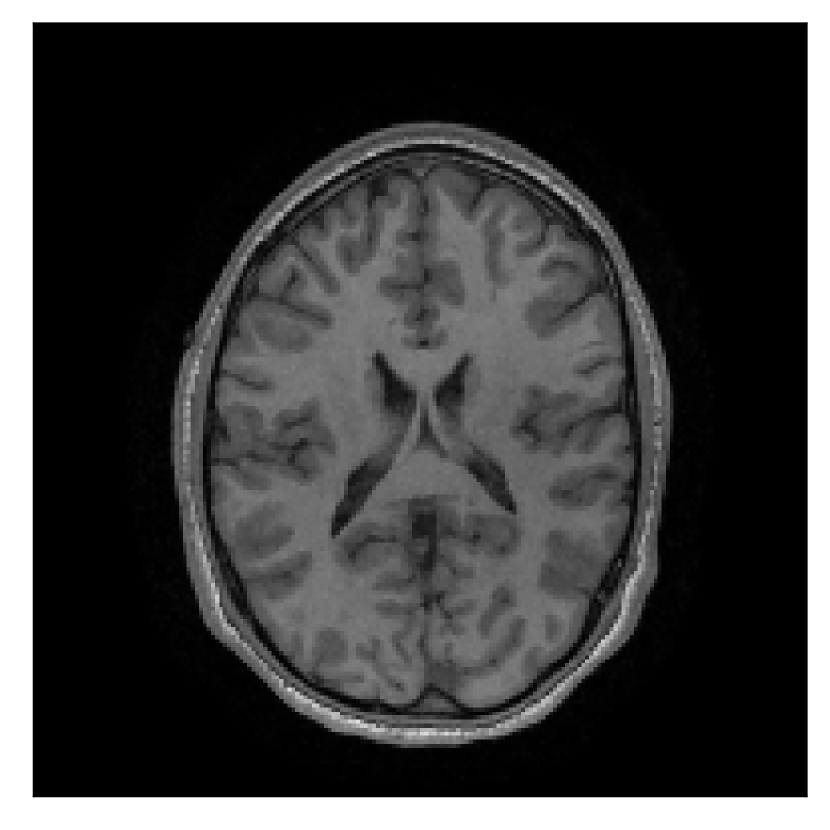

4.3 Experiment 3: scanner reconstruction vs raw k-space data

The results of the two experiments described in Section 3.3 are depicted in Figures 12 and 14. The main difference between the two experiments is related to the input data for the proposed motion-correction algorithm.

In the first experiment, the corrupted contrast has been acquired with a protocol based on a linear filling pattern in -space. Note that, in this particular case, the scanner reconstruction implements the SENSE method. We then extracted the DICOM of both amplitude and phase produced by the scanner, and used it as input data (after a Fourier transform) for the algorithm. The proposed scheme is able to successfully remove the motion artifacts in Figure 12.

| Section 3.3, Figure 12 | Sagittal | 22.26 | 27.54 | 0.6963 | 0.8409 |

| Coronal | 23.46 | 31.65 | 0.7321 | 0.8370 | |

| Axial | 24.55 | 32.33 | 0.7895 | 0.8144 | |

| Section 3.3, Figure 12 | T2 | Completely corrected | No blurring | No additional artifacts | |